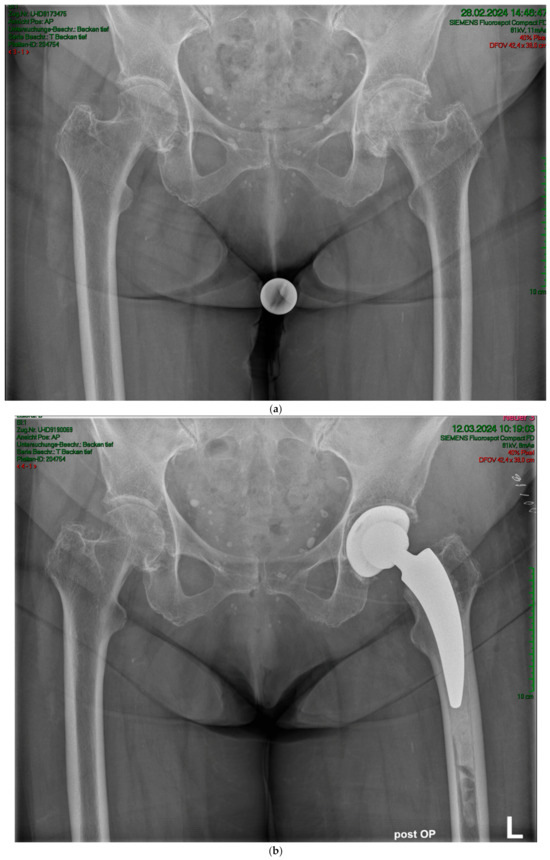

Figure 3.

(a) Case #2: Osteoarthritis, female, 85 years old, bilateral sequential implantation of an A2 stem, Dorr B-C femora. (b) Left side: slight distalization of the cement stopper. (c) Right side: no positional change of the cement stopper during the operation.